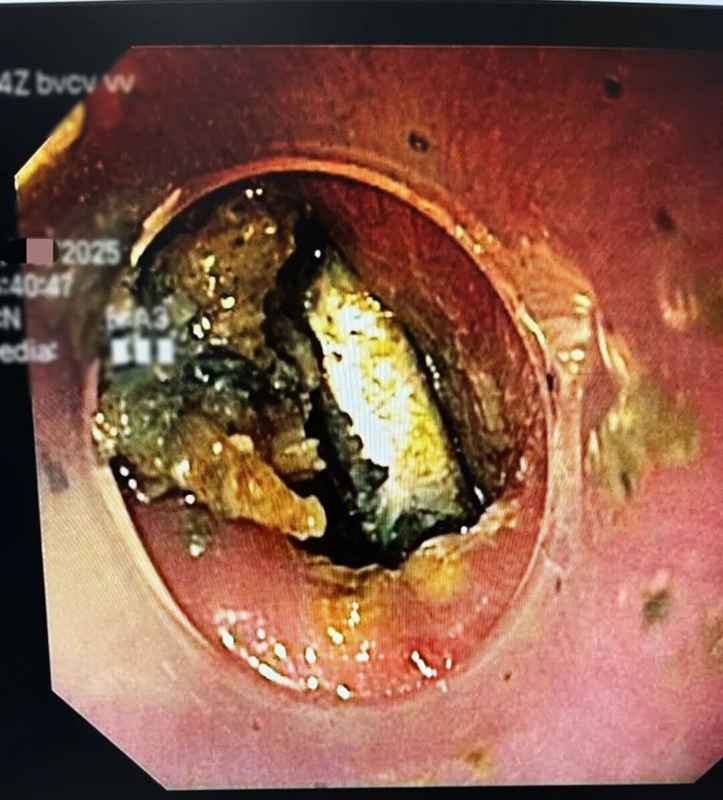

术前检查刚一完成,医师便迅速开展胃镜手术,此时画面让人揪心:纽扣电池已牢牢嵌顿在食管处,周围黏膜不仅明显水肿,还出现了黑焦样的腐蚀痕迹。

这枚“滚刀肉”般的纽扣电池取出难度极大,医师凭借精准操作,终于用异物钳将其成功取出。若再晚一步,可能导致食管穿孔、大出血,甚至危及生命。